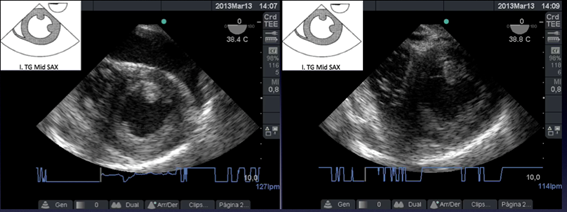

Figura g: Imágenes transgástricas a 0 grado donde se ve taponamiento cardíaco con compresión del ventrículo derecho(VD) y luego del drenaje expansión del VD

Paciente con PC al que se colocó ETE y luego de descartada una alteración estructural cardíaca, se observa un analítico con acidosis metabólica severa con hiperpotasemia como causa de PC en diástole. (Figura i)